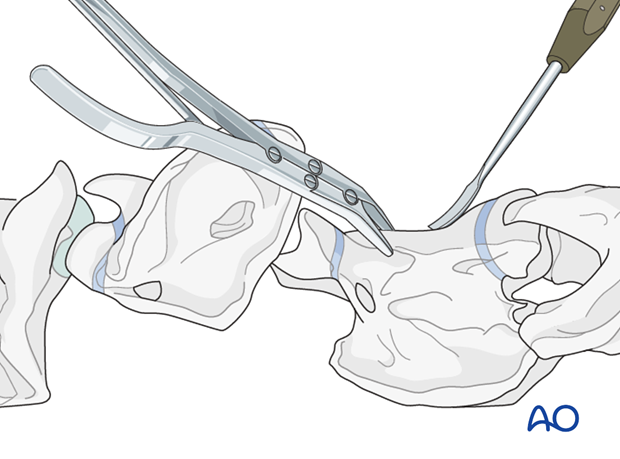

This procedure is performed with the patient positioned in dorsal recumbency through the ventral midline approach to the cervical spine.

The ventral spinous process of the body of C2 is flattened slightly using a curved osteotome and bone rongeur.

After exposing the ventral surfaces of the atlas and axis, the alignment of the vertebrae is corrected and maintained with bone-holding forceps.